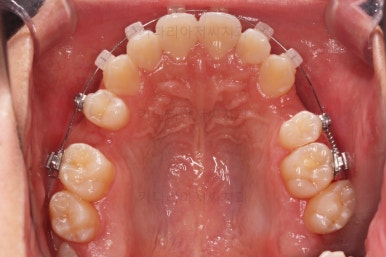

초진 시 입안의 모습입니다.

앞니가 많이 삐뚤고, 송곳니가 부각되어 덧니처럼 보이네요.

장치를 처음 부착한 모습입니다.

이번 환자분이 선택하신 장치는 데이몬 클리어라고 하는 자가결찰 세라믹 장치인데요.

순차적으로 장치를 붙여가며 치아를 가지런하게 합니다.

가지런하게 하는 단계를 거친 뒤,당기기 과정에 들어가는데요.